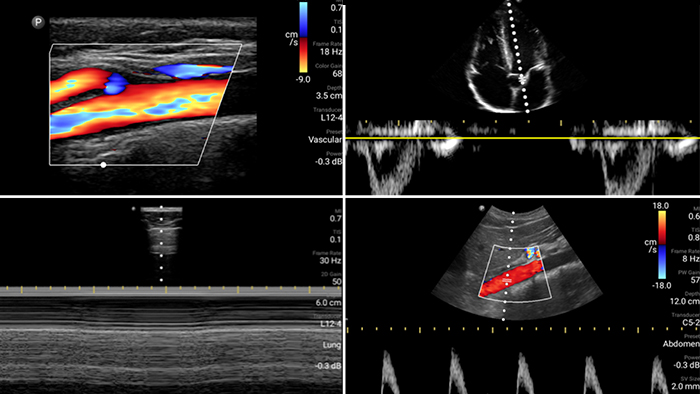

Evaluate, diagnose and treat your patients in minutes with a multi-point POCUS exam.

Lumify can help assess patients faster and improve accuracy when diagnosing common causes of dyspnea and other lung conditions.

Heart attack patients need immediate care. Lumify's cardiac presets can help patients get diagnosed faster to improve their outcomes.

• 4 to 1 MHz extended operating frequency range • 2D, color Doppler, M-mode, advanced XRES and multivariate harmonic imaging • High-resolution imaging for abdominal and cardiac applications: Cardiac, OB/GYN, Lung, Abdomen and FAST imaging preset optimizations Lumify aids life-saving technology in prehospital setting